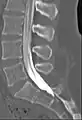

Myelogram showing arachnoiditis in the lumbar spine.

Myelography is a type of radiographic examination that uses a contrast medium to detect pathology of the spinal cord, including the location of a spinal cord injury, cysts, and tumors. Historically the procedure involved the injection of a radiocontrast agent into the cervical or lumbar spine, followed by several X-ray projections. Today, myelography has largely been replaced by the use of MRI scans, although the technique is still sometimes used under certain circumstances – though now usually in conjunction with CT rather than X-ray projections.